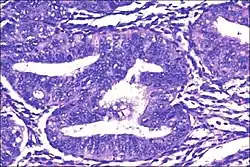

| Micrograph showing simple endometrial hyperplasia, where the gland-to-stroma ratio is preserved but the glands have an irregular shape and/or are dilated. Endometrial biopsy. H&E stain. | |

Like other hyperplastic disorders, endometrial hyperplasia initially represents a physiological response of endometrial tissue to the growth-promoting actions of estrogen. However, the gland-forming cells of a hyperplastic endometrium may also undergo changes over time which predispose them to cancerous transformation. Several histopathology subtypes of endometrial hyperplasia are recognisable to the pathologist, with different therapeutic and prognostic implications.[4]

- Endometrial hyperplasia (simple or complex) - Irregularity and cystic expansion of glands (simple) or crowding and budding of glands (complex) without worrisome changes in the appearance of individual gland cells. In one study, 1.6% of patients diagnosed with these abnormalities eventually developed endometrial cancer.[7]